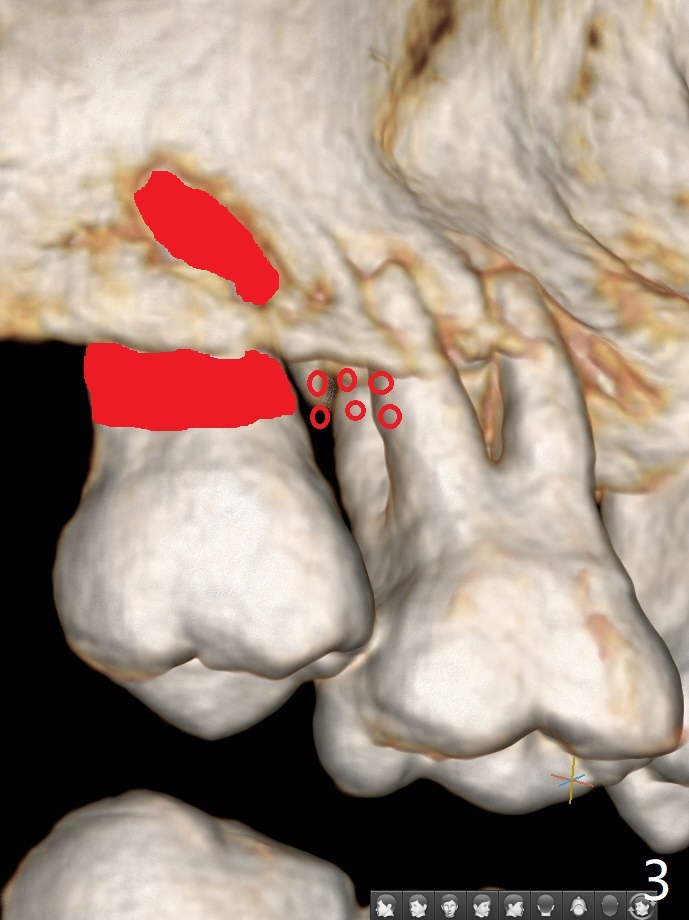

45岁女右上7严重骨质吸收终于开始出现症状(图一),虽然邻牙(6)骨质吸收也明显(图二,四,六,八,十),但是保留它,远中颊侧(DB),腭侧(P)根成为骨粉(图三,五,七,九,十一:红圆圈)支架。